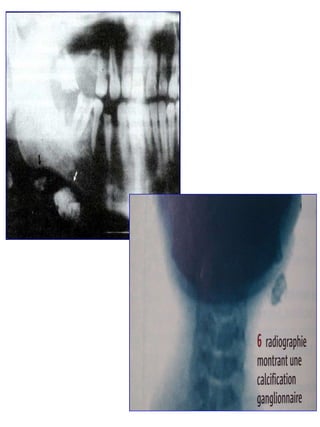

2-2-  Imagerie:    Radiographies: - Panoramique, clichés standards;  - thoracique dans le cadre d’une tuberculose, sarcoïdose ou un bilan carcinologique.     TDM: - La tomodensitométrie avec injection permet d’apprécier les rapports de volumineux Adn avec les structures adjacentes, à la recherche d’un envahissement pathologique. Il permet de juger l’opérabilité en cas de volumineux Adn.     Échographie: - Elle peut retrouver des Adns infra cliniques;     IRM, angiographie: - Limites:  *  ne permet pas d'affirmer le caractère bénin ou malin d'une masse ganglionnaire cervicale.  *  Les tumeurs salivaires bénignes ne peuvent parfois être distinguées des adénopathies. - Diagnostic différentiel avec une masse tumorale maligne, une cavité kystique, ou les tumeurs vasculaires; - Permet d'évaluer correctement l'envahissement des structures vasculaires cervicales par des processus malins.

2-2- Imagerie: Radiographies: - Panoramique, clichés standards; - thoracique dans le cadre d’une tuberculose, sarcoïdose ou un bilan carcinologique.  TDM: - La tomodensitométrie avec injection permet d’apprécier les rapports de volumineux Adn avec les structures adjacentes, à la recherche d’un envahissement pathologique. Il permet de juger l’opérabilité en cas de volumineux Adn.  Échographie: - Elle peut retrouver des Adns infra cliniques;  IRM, angiographie: - Limites: * ne permet pas d'affirmer le caractère bénin ou malin d'une masse ganglionnaire cervicale. * Les tumeurs salivaires bénignes ne peuvent parfois être distinguées des adénopathies. - Diagnostic différentiel avec une masse tumorale maligne, une cavité kystique, ou les tumeurs vasculaires; - Permet d'évaluer correctement l'envahissement des structures vasculaires cervicales par des processus malins.